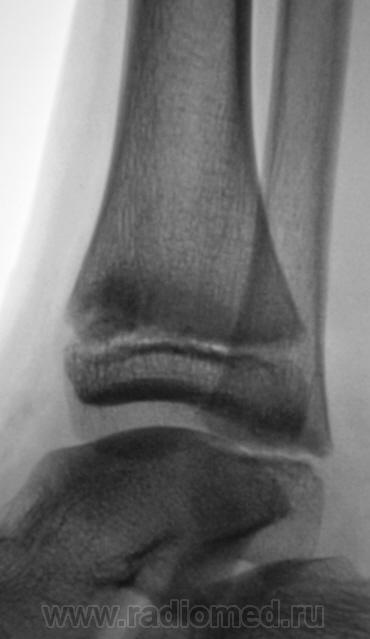

Уважаемый Валентин Львович! А что в жалобах, анамнезе? В переднемедиальной зоне дист. метафиза б/берцовой кости субхондрально под зоной роста участок уплотнения к/структуры, не отграниченный от неизмененной костн. ткани. Возможно, это импрессионный перелом? или остеонекроз? Смущает небольшой очаг аналогичной структуры в таранной кости под медиальным валом блока.

Клиника перелома. Травма - за 4 часа до исследования.

Согласен с коллегой helenmar по поводу перелома по типу импрессии, а ещё подвывих стопы в г/стопном суставе.

А как же объяснить асимметрию рентгеновской суставной щели?

А на мой взгляд, суставная щель вполне симметрична.

А, что, это за фрагментик?

У взрослого такие соотношения в суставе назову супинационным подвывихом, хотя прямая проекция не оптимальна для такого заключения, боковая вовсе косая.